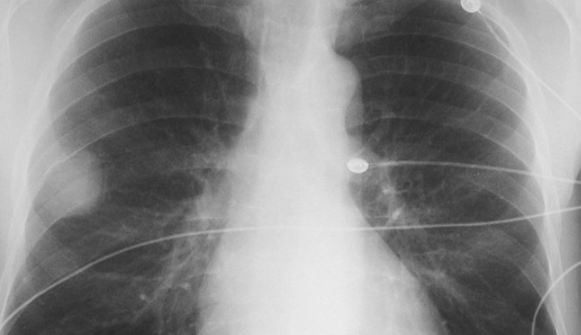

폐결절은 폐 안에 생긴 3cm 이하의 고형성 음영 또는 병변을 말합니다. 일반적으로 건강검진에서 시행하는 흉부 X-ray에서는 발견되지 않는 경우가 많으며, CT 검사에서 우연히 발견되는 경우가 많습니다.

결절의 모양은 다양할 수 있으며, 일부는 과거 감염, 섬유화, 염증의 흔적일 수 있습니다. 문제는 이러한 결절이 폐암 초기일 가능성도 있기 때문에, 무조건 안심할 수 없다는 데 있습니다.

하지만 많은 연구에서 폐결절의 상당수가 양성으로 확인되며, 전체 결절 중 악성일 확률은 5~10% 정도라고 알려져 있습니다. 그러므로 폐결절이 곧 폐암이라는 공포로 이어질 필요는 없습니다.